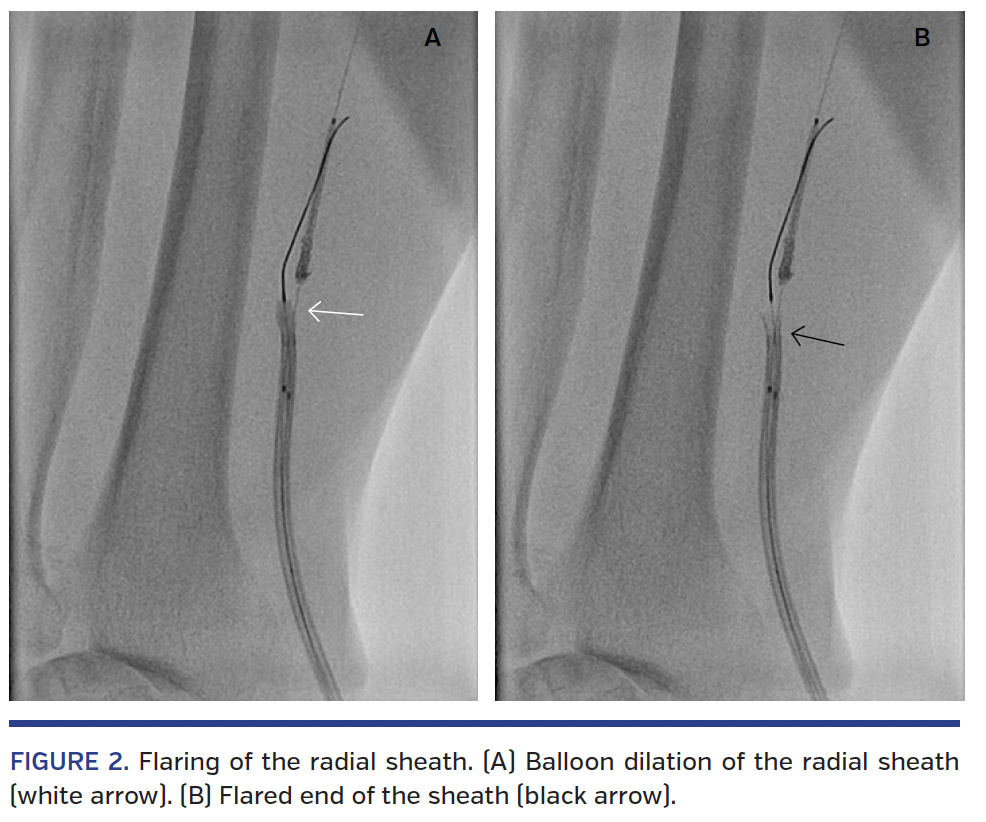

An attempt to push the stent further with uncontrolled guide-catheter movement led to stripping the stent off the balloon and crushing its proximal half (the “concertina” effect), which was stuck in the vessel wall due to the jagged edges (Figure 1A). All attempts to pull the stent back into the guide failed. At this stage, a small 0.85 mm balloon mounted on a second wire was placed just beside the crushed stent and inflated at low pressure to free its edges. We then used a novel, simple technique to extract the crushed stent safely out of the coronary whereby a 2.5 mm balloon was used to dilate the mouth of the guide to stretch this open wide (Figure 1B). Subsequently, the jagged proximal edge of the stent was successfully pulled into the guide (Figure 1C) and the entire system (guide, stent, and wire) was then withdrawn backward (Video 1). At the radial sheath, the bulky stent got stuck again and the distal end of the radial sheath was dilated with the 2.5 mm balloon flaring it up (Figures 2A and 2B; Video 2). Finally, the stent was completely retrieved (Figure 3A; Video 3) and a final angiogram showed no vascular damage.

By dilating the distal ends of the guide and the sheath with the use of a compliant balloon that is slightly larger than their respective inner diameters to flare the distal ends, balloon-assisted stent retraction can be a simple and safe way to retrieve a damaged stent.